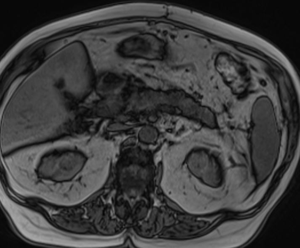

МР-диагностика образований почек